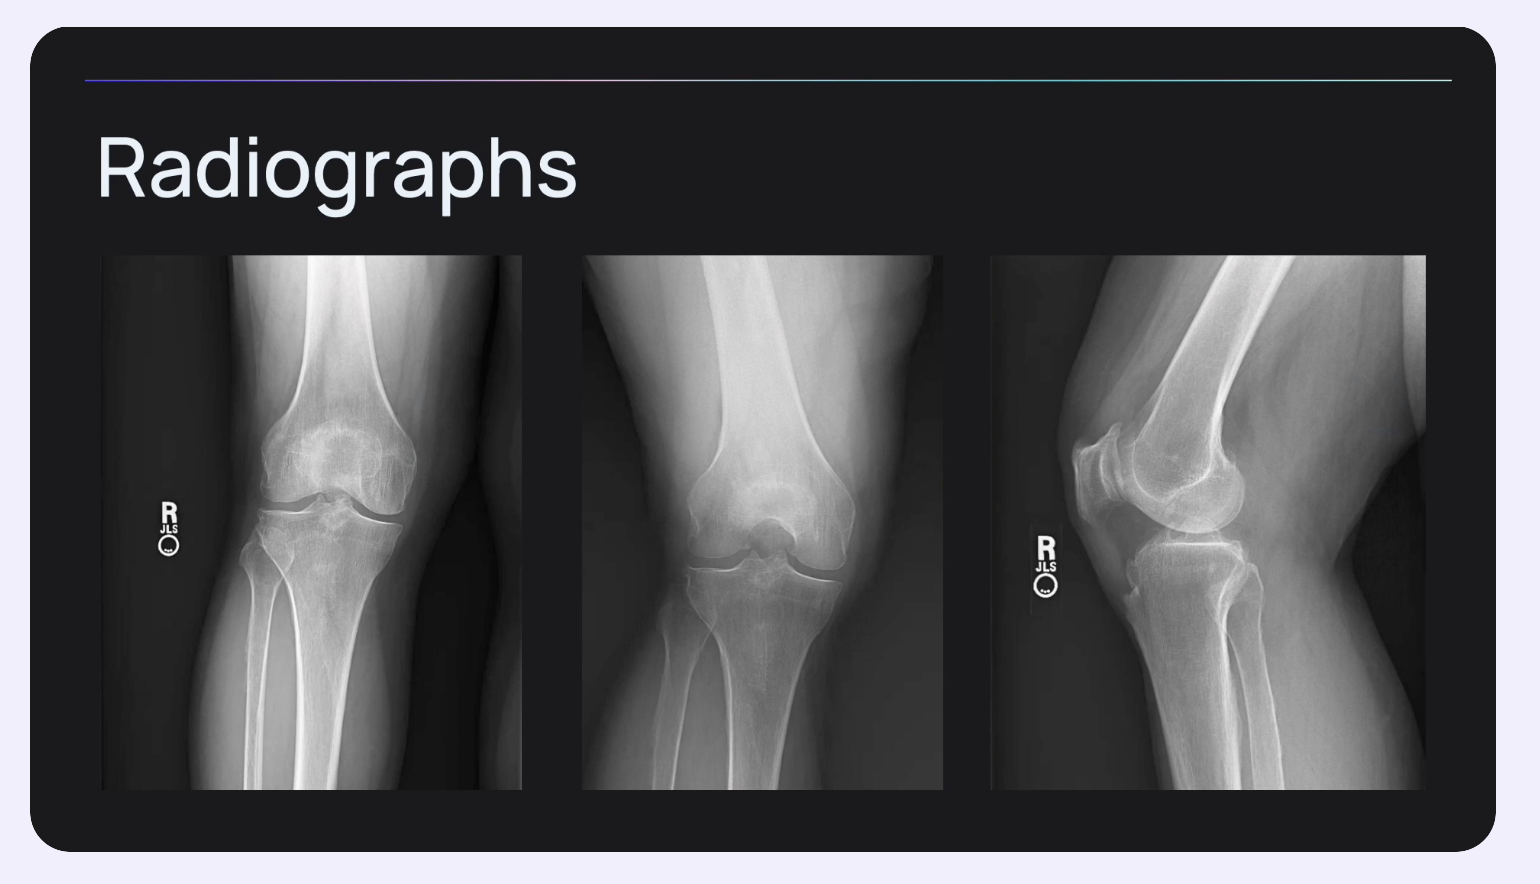

Dr. Christian Anderson presents a clinical case of a medial meniscus root tear, discussing biomechanics, MRI diagnosis, surgical tunnel placement, and the importance of retensionable fixation to restore native knee function and prevent arthritis progression.